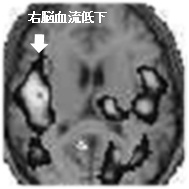

ガンマカメラ(核医学検査)は、ごく微量の放射線を放出する検査薬を投与して診断を行います。身体の中に入った検査薬は、脳、心臓、腎臓、骨など、特定の臓器や腫瘍等に集まり、ガンマ線を放出します。これらの分布を画像化するための診断装置を「ガンマカメラ」と呼んでいます。当センターでは、主に脳血流検査及び心筋血流検査や全身の骨の検査などを行っています。検査による放射線の被ばくは、胃のX線検査や自然界の放射線の量と同程度ですので、検査を受ける本人や周辺の人への影響は心配ありません。![]() |